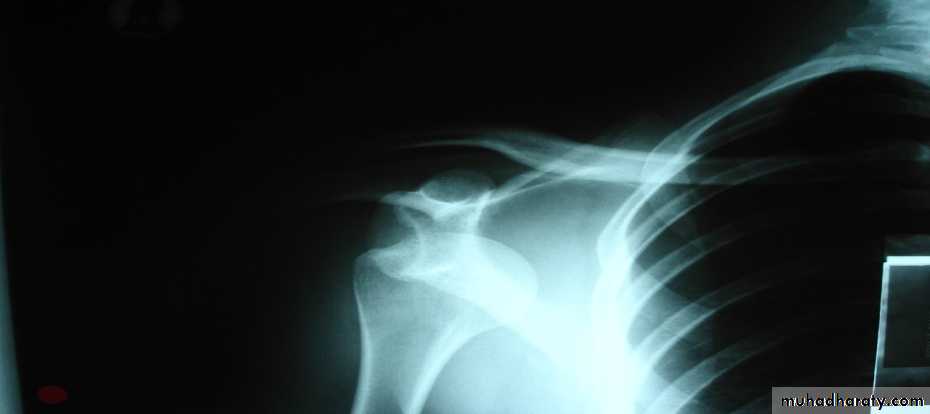

Hill – Sachs lesionBankart lesion

Recurrent dislocation

Surgery is indicated if ≥ 3 times per year